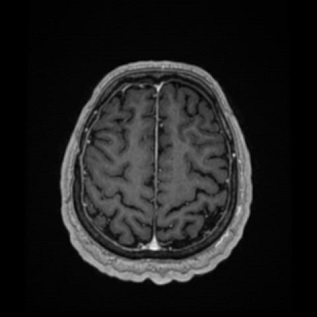

Case description: A 59-year-old Caucasian man presented with transitional episodes of tinnitus and an unspecific headache. Imaging studies (magnetic resonance imaging – MRI) demonstrated a thickened dura mater. Lymphoma was suspected due to an abnormal flow cytometric analysis of a cerebrospinal fluid (CSF) sample. Hematological diagnostics including bone marrow biopsy, whole body computed tomography (CT) and digestion tract examination were performed leading to the exclusion of hematological malignancy. The patient underwent surgery, and a specimen from the lesion was obtained. On this basis, intracranial idiopathic hypertrophic pachymeningitis was diagnosed. First line treatment strategy was introduced with corticosteroids with a gradual dose reduction. After the 48-month follow-up, we observed an alleviation of symptoms with a gradual significant decrease in the thickening of dura matter with almost complete resolution.